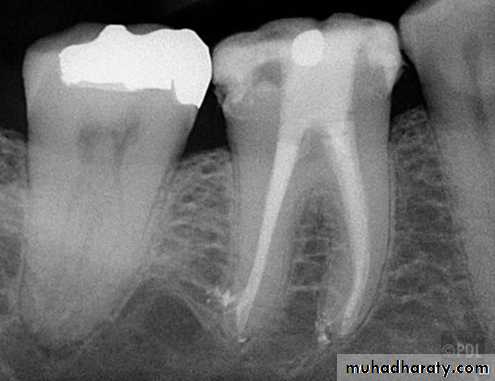

1- Thermo plasticized injectable gutta percha: heating gutta percha to a molten state and then forcing it under mechanical pressure ̏injection” in to the root canals. Injection of the gutta percha produce a good seal, but extrusion of the material from the root apex is possible.Advances in gutta percha

ObturaUltrafil

2- Gutta percha carrier devices: (Thermafil)

These are cores of metal or plastic coated with gutta percha. They are heated in an oven and then simply pushed into the root canal to the correct length. The core is then cut with a bur. A dense filling results, but apical control is poor and extrusions common. They are expensive and difficult to remove.Advances in gutta percha